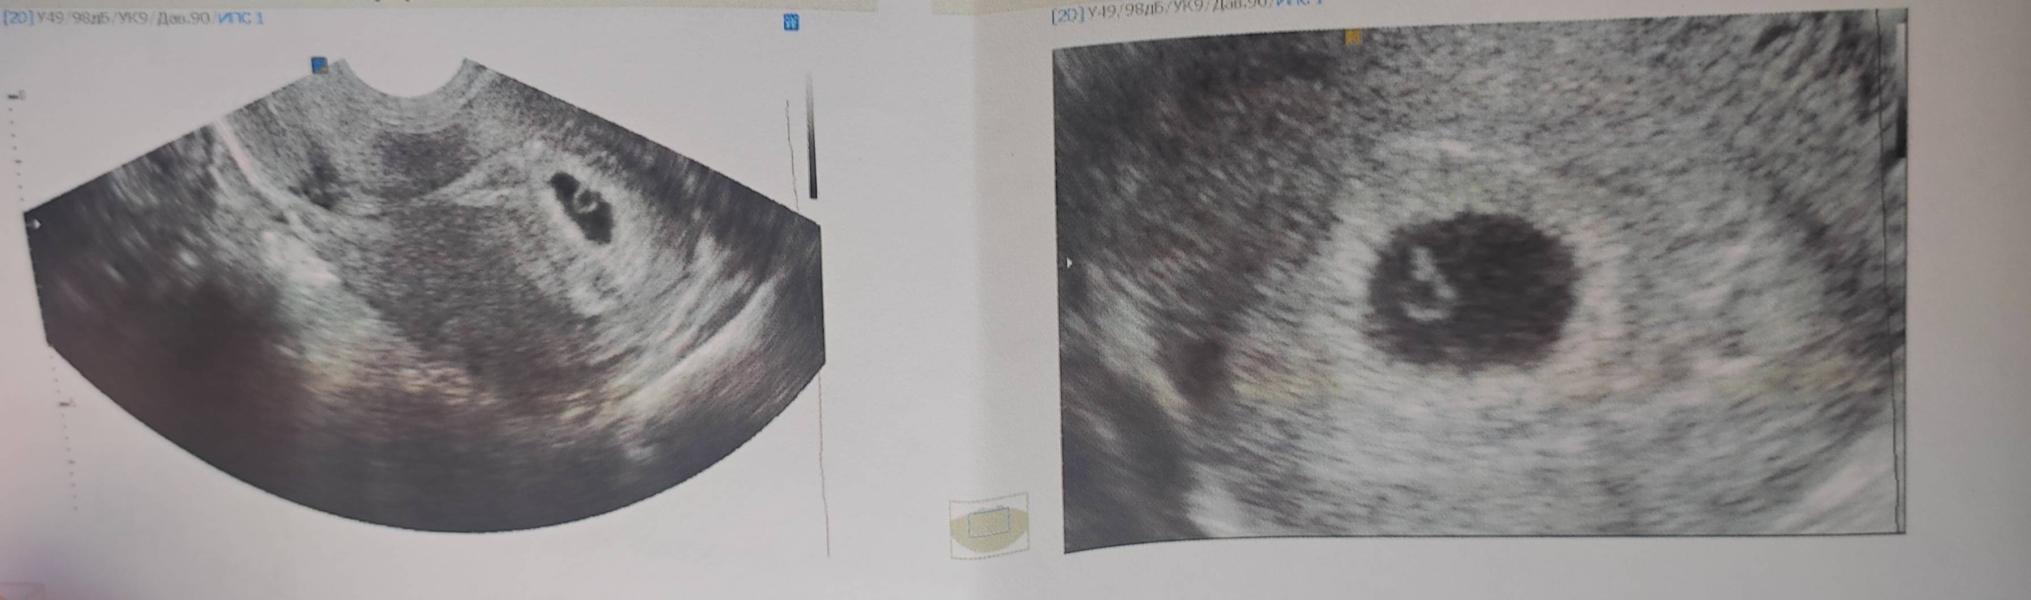

УЗИ показало эмбрион, но нет сердцебиения - это нормально?

Сделала УЗИ.

Эмбриончик визуализируется, ура! Сердцебиения четкого пока нет, услышали только пульсацию, надеюсь через недельку уже будет отчетливо 🙏

А кисты на яичниках никуда не делись... Будем наблюдать.